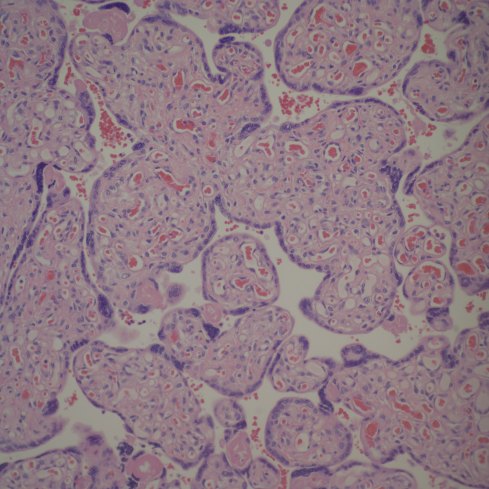

While some have suggested chronic hypoxia as a cause of chorangiosis, I think that is unlikely for two reasons [4, 5, 15-17]. First I don’t see hypervascular villi with chronic utero-placental ischemia even in stillborn infants, many of whom likely had become hypoxic. Second, increasing the capillaries does not necessarily increase oxygen transport to the fetus. See Mayhew and colleagues discussion of the relative role of parameters of oxygen transfer in the placenta[18]. Keeping most parameters within physiological limits, the only important variable is the thickness of the barrier between the maternal and fetal circulation. Another possible mechanism of chorangiosis is a varicose vein of the villi mechanism in which back venous pressure is the cause. I think this is unlikely since the usual effect of elevated umbilical venous pressure is hydrops. A third theory is a genetic or acquired mismatch in growth factors, e.g. witness the extreme capillary proliferation in mesenchymal dysplasia of the placenta of which one cause is the imprinting error in Beckwith-Wiedemann syndrome. There is a case report of chorangiosis associated with elevated maternal HCG late in pregnancy[19], which may be a clue to a type of mechanism. The following figure 4 shows the abrupt onset of capillary proliferation from a stem villus in a placenta submitted for “probably Down Syndrome” that might have a genetic basis.